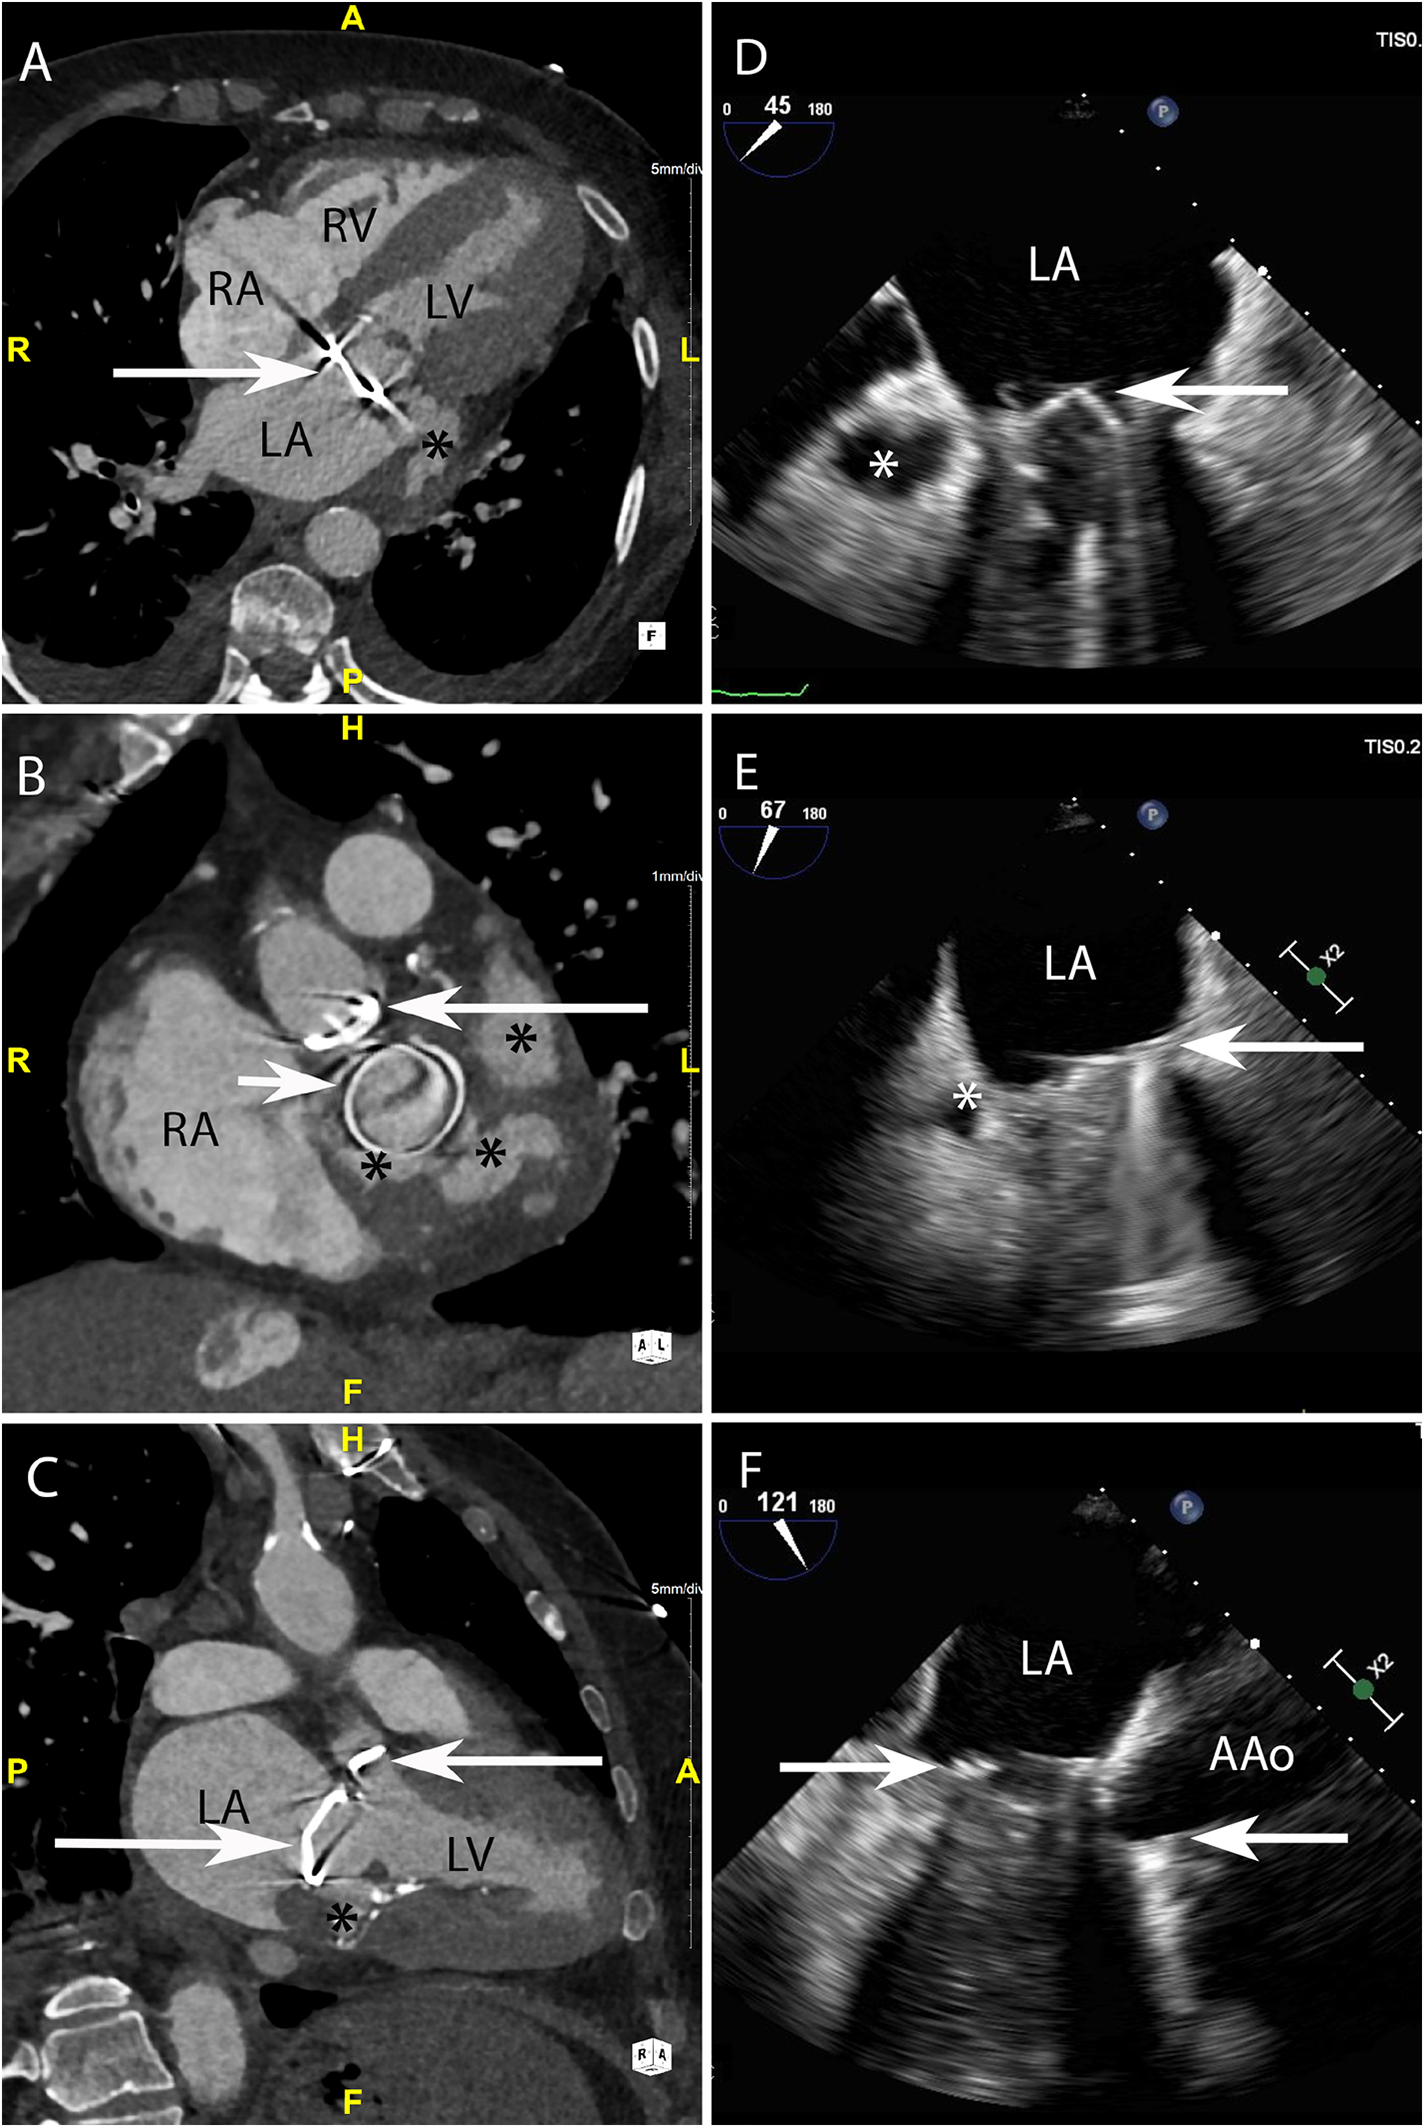

Figure 4

CASE 4 - A 79-year-old man with metallic mitral and aortic valve prostheses undergoing treatment for IE remained febrile and unwell despite appropriate guideline recommended antibiotic therapy (see text). RA, right atrium; RV, right ventricle; LA, left atrium; LV, left ventricle; AAo, ascending aorta.

A 79-year-old man with metallic mitral and aortic valve prostheses (arrows) undergoing treatment for IE remained febrile and unwell despite appropriate guideline recommended antibiotic therapy. Blood cultures remained positive for Staphylococcus aureus. Cardiac CT was performed: Axial (Figure 4A) and in-plane (Figure 4B) views demonstrated a multi-lobulated thick walled paravalvular pseudoaneurysm (asterisks) (HU 231) which extended posteriorly and laterally to the sewing ring of the valve prosthesis. Oblique sagittal 2-chamber (Figure 4C) demonstrated additional inferior extension of the pseudoaneurysm (asterisk). Preceding TOE images taken from the ME mitral commissural (Figure 4D), ME 2-chamber (Figure 4E) and ME 3-chamber (Figure 4F) views showed a likely paravalvular pseudoaneursym (asterisk) but its extent or size could not be adequatly determined leading to a CT being performed.